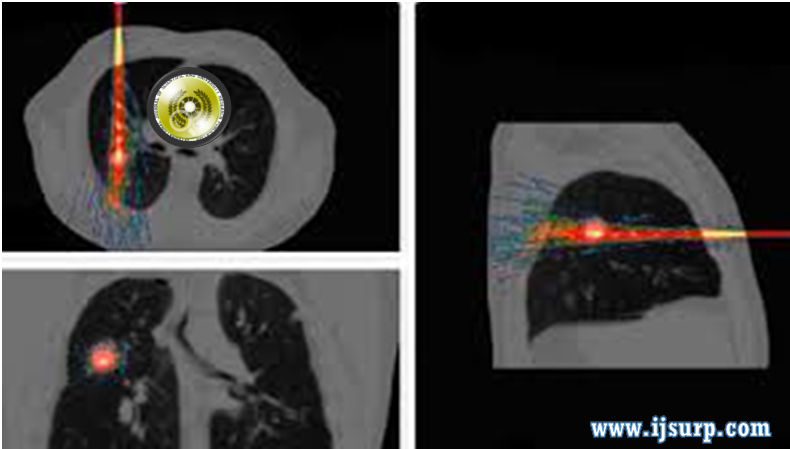

GATE, a Geant4-based simulation platform for PET integrating movement and time management

Abstract : the Geant4 Application for Tomographic Emission, is a simulation platform developed for PET and SPECT. It combines a powerful simulation core (the Geant4 toolkit) and a large range of developments dedicated to nuclear medicine. In particular, it models the passing of time during real acquisitions, allowing to handle dynamic systems such as decaying source distributions or moving detectors. We present several series of results that illustrate the possibilities of this new platform. The simulation of decaying sources is illustrated on a dual-isotope acquisition with multiple time-frames. Count rate curves taking into account random coincidences and dead-time are shown for a dual-crystal set-up and for a small-animal PET scanner configuration. Simulated resolution curves and reconstructed images are shown for rotating PET scanners. Lastly, we present comparisons of simulated point-spread functions and spectra with experimental results obtained from a small-animal gamma camera prototype.

Keywords :PET and SPECT applications that include scanner design, statistical image reconstruction, scatter correction, protocol optimization